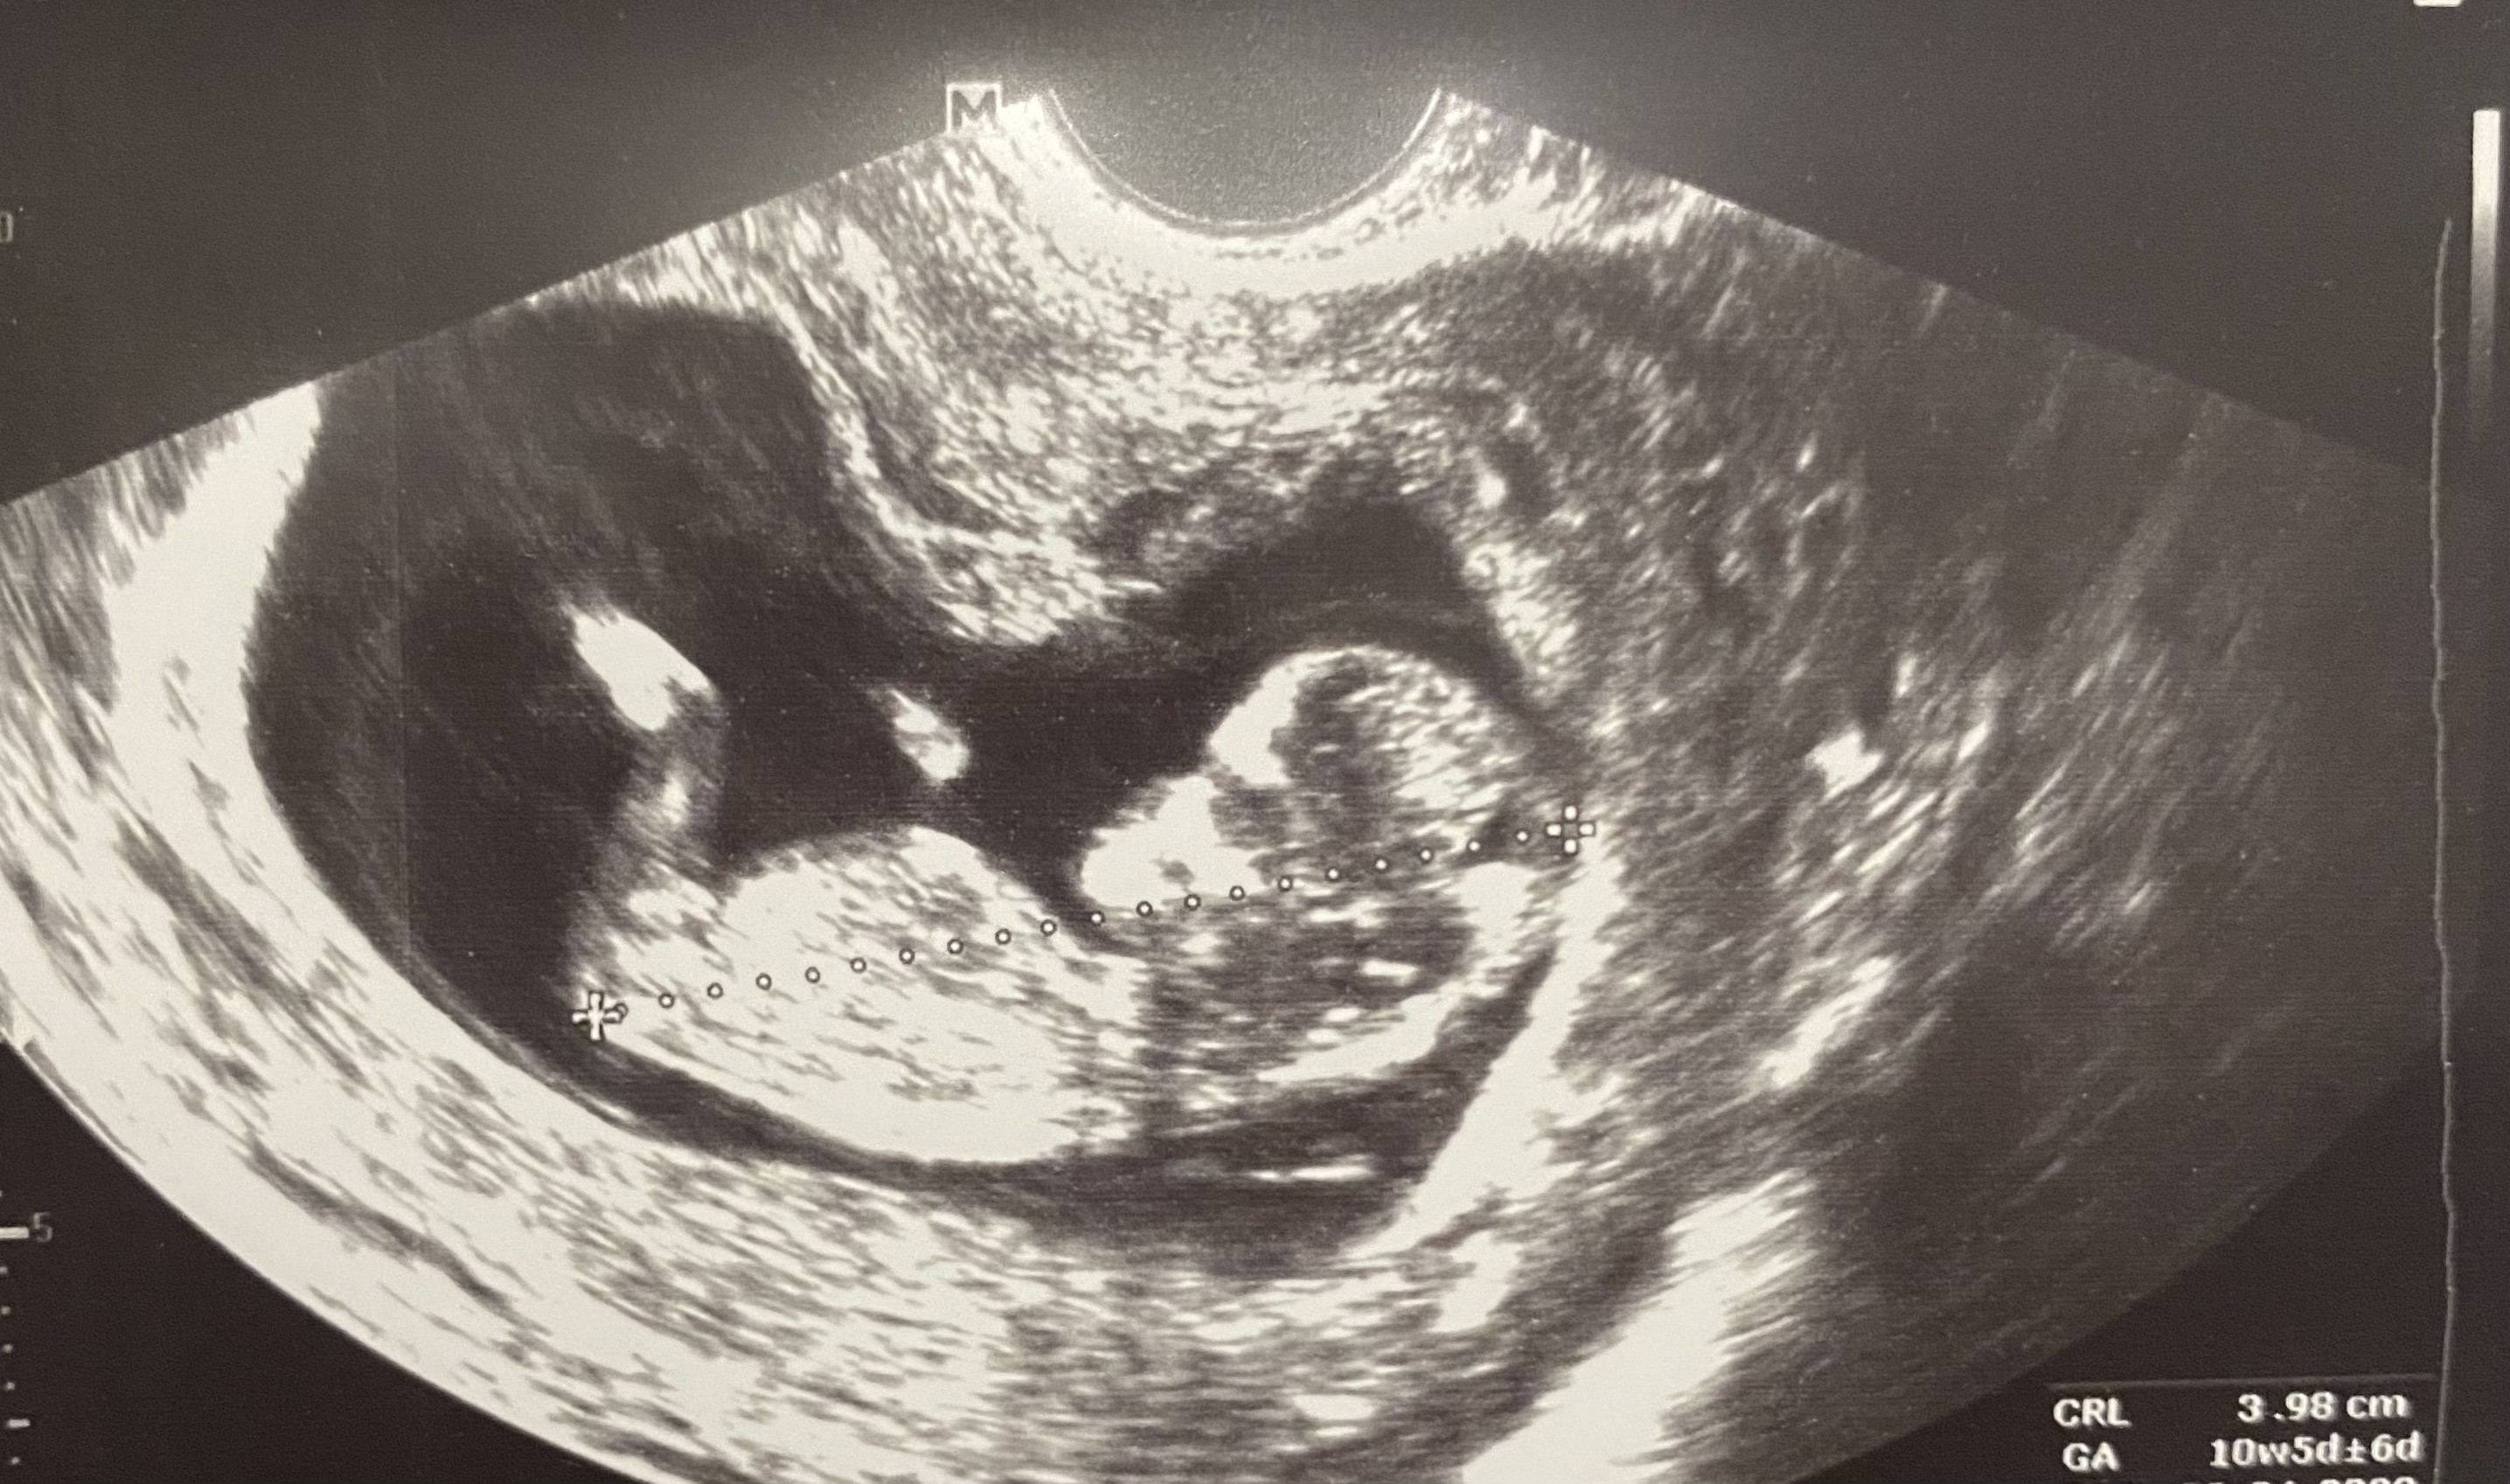

Przypałętała się do mnie infekcja grzybicza, byłam wczoraj na wizycie i mam zalecenie żeby próbować zaleczyć to probiotykiem z kwasem mlekowym i do tego podmywać się jakimś tam specjalnym płynem, bo do 12 tygodnia niezbyt wiele jesteśmy w stanie z tym zrobić, jak nie przejdzie to po 12 tygodniu można już włączyć jakieś leczenie. No i okej, liczę że się uda i że przejdzie albo chociaż się uspokoi. Z tym, że na jutro jestem zapisana na usg i teraz nie wiem czy iść czy nie… aktualnie wszystko tam na dole mam mega opuchnięte i boli więc trochę obawiam się usg dopochwowego. Z drugiej strony zastanawiam się czy nie zacisnąć zębów i jakoś tego nie przetrwać, bo w Medicoverze mam skierowanie na usg poniżej 10 tygodnia a jutro już będzie 9+3. Wątpię, że tak łatwo przepiszę wizytę na początek kolejnego tygodnia, tym bardziej że dopiero wracam z urlopu i od razu wolnego nie wezmę